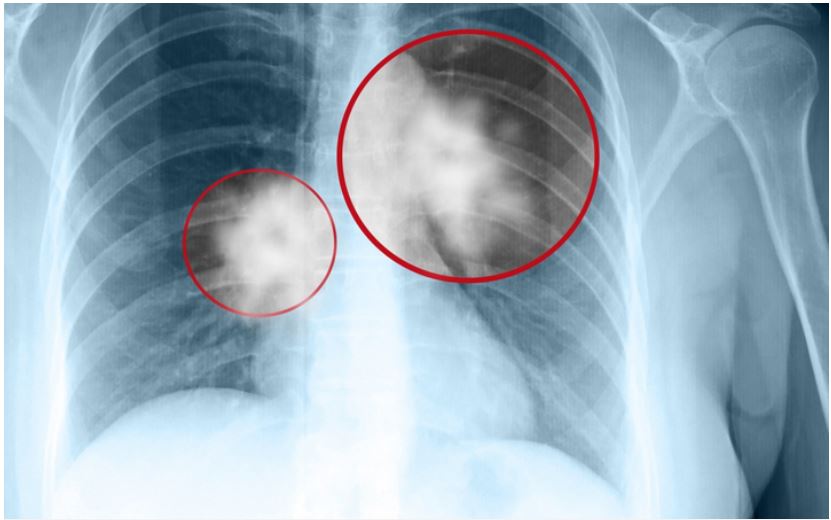

Chụp X-quang ngực

Chụp X-quang ngực là kỹ thuật giúp chụp lại các cơ quan và khung xương trong lồng ngực. Tia X-quang có khả năng xuyên qua cơ thể và tạo ra hình ảnh của các bộ phận bên trong. Phương pháp này có thể phát hiện các bất thường hoặc khối u tại phổi, tuy nhiên, đối với các khối u quá nhỏ, hiệu quả của X-quang không cao. Vì vậy, bác sĩ thường kết hợp chụp X-quang với phương pháp chụp CT lồng ngực.